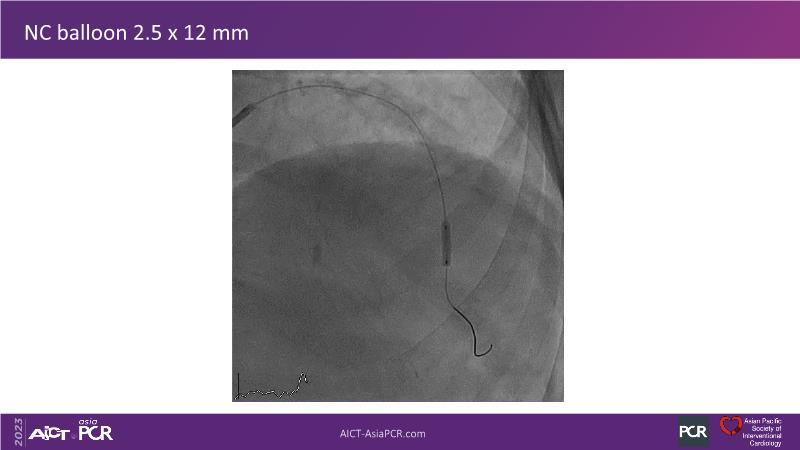

• To see advantages of RotaCUT as part of lesion preparation in left main bifurcation